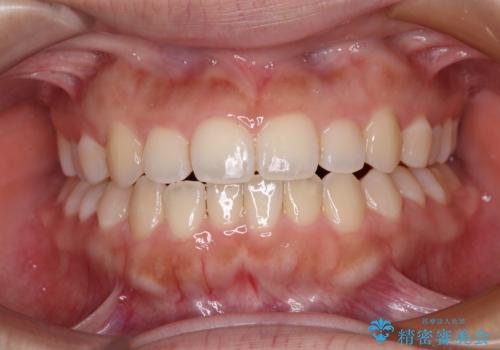

前歯のクロスバイトを改善 インビザライン・モデレートによる矯正治療

- 上下前歯のクロスバイトと叢生を気にして来院された患者様です。

インビザラインでの治療を希望されていて、デコボコの程度が中等度であり、安価なパッケージにて対応可能と判断されたため、インビザライン・モデレートを用いて矯正治療を行うこととしました。